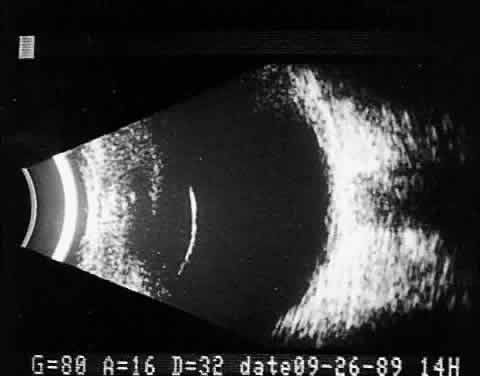

Tumors with great acoustic heterogeneity, such as choroidal hemangiomas, where adjoining cell and tissue layers have marked differences in acoustic impedance, create large echo amplitudes at each interface. These tumor types have typical high internal reflections at each major interface. These high internal reflections make the lesions appear solid white in B-scan displays and produce highamplitude spikes during A-scan imaging (Fig. 12).

Fig. 12. Contact B-scan and simultaneous A-scan: choroidal hemangioma. Ultrasonically heterogeneous tissue shows strong reflectivity at all levels, appearing white in B-scan gray scale.